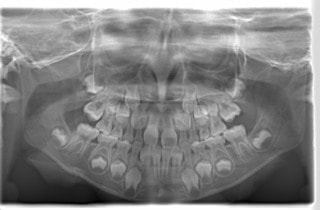

小児期ケース:反対咬合+上顎両側3番埋伏歯

(受け口+右上3番目の永久歯が埋まってしまい、はえてこない)

治療法:上顎急速拡大装置+クリアスナップ+フェイスマスク+上顎右側3番は開窓萌出誘導

(難症例のため、小児期の矯正を2段階にわけました)